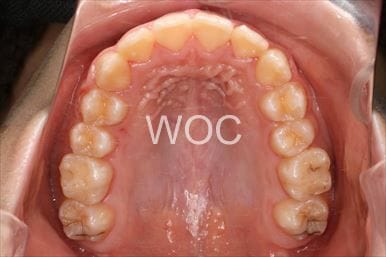

八重歯・叢生マウスピース型(カスタムメイド)矯正装置(インビザライン)

マウスピース型(カスタムメイド)矯正装置(インビザライン)を希望。ガタガタ(叢生)が強く上顎両側第一小臼歯抜歯か非抜歯のボーダーラインケースだったが、装置装着時間の協力も良く非抜歯で終了となりました。

- 年齢:35歳女性

- 主訴:ガタガタ

- 基本矯正料金:88万円

- 治療期間:2年6ヶ月

- 非抜歯

-